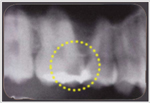

| A.歯の構造は、表面からエナメル質⇒象牙質⇒歯髄(神経)となっています。歯髄には血管と神経が通っていてエナメル質・象牙質に栄養と免疫成分を供給しています。いったんむし歯になってしまうと、むし歯菌がエナメル質・象牙質を破壊していきます。 このむし歯菌は象牙質の奥深く(象牙細管)まで進入します。歯を大きく削ってしまうと、すでに象牙細管に侵入したむし歯菌が歯髄にまで達してしまい痛みがでてきます。レントゲンでは大きなむし歯が写っているのに痛みがない場合は、むし歯菌が歯髄(神経)の一歩手前で止まっている状態と考えられます。このような状態のときにドックベストセメントを用いて象牙細管内のむし歯菌を殺菌して、象牙細管の穴を封鎖すれば麻酔をしなくても痛みなく治療ができるのです。 ![]() |

| ※薬を使ってむし歯を柔らかくして全部かきとるカリソルブ(Carisolv、カリソリブ、自費診療で¥10,000~¥20,000)という治療方法がありますが、この方法よりもドックベストセメントによるむし歯治療の方が優れています。カルソルブでは、象牙細管内のむし歯菌を殺菌することができません。カリソルブの適応はC1、C2といわれる小さなむし歯だけで、歯と歯の間のむし歯やC3に近い深いむし歯は適応外です。ドックベストセメントは乳歯にも適用可能ですが、あと数カ月で抜けてしまうような場合は、ドックベストセメントを使用しません。 |